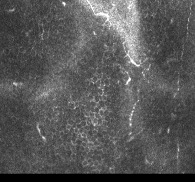

LASIK: quasi disparition des nerfs cornéens en microscopie confocale SMILE: préservation de nombreux nerfs cornéens